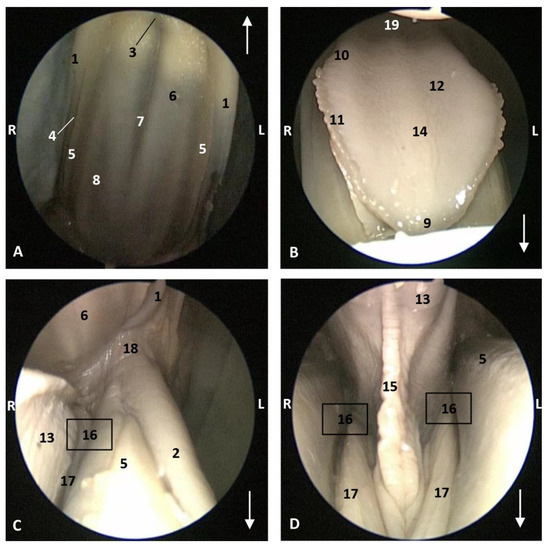

The endoscopic study began at the oropharynx, showed a tightly closed isthmus of the fauces in a young fetus, a Delphinus delphis (dde2). The endoscope could not cross this gate (Figure 16).

The endoscope was passed into the fauces in an older fetus, a Delphinus delphis (dde3) showing a bright mucosa. No lymphoreticular tissue in the floor (tongue), walls (palatoglossus archs or folds) or roof (soft palate) of the fauces was observed. The soft palate is inserted into the ventral crest formed between the lateral and medial lamina of the pterygoid bones. The palatoglossal archs or folds connect to the soft palate through the tongue root. At the end of fauces a soft vallecula continues dorsally with the lingual aspect of the mucosa of epiglottic cartilage. At this level we dorsally observed the intrapharyngeal orifice to allow entry of the larynx into the nasopharynx. Additionally, the laryngopharynx begins with a piriform recess on either side of the larynx cartilages. The left piriform recess is wider than the right one. The dilated oesophageal vestibule is caudal to the recesses whose mucosa is arranged in longitudinal folds changing to small quadrangular folds where the oesophageal mucosa begins (Figure 17).

Both the Stenella coeruleoalba (scop1) and Globicephala melas (gma1) fetuses had a well-developed mucosa at the isthmus and only a narrow passage to the fauces which had a pale lingual mucosa and a grey/brown colour in its walls and roof (Figure 18 and Figure 19).

A well-defined fauces was observed in an older Delphinus delphis (dde8) and also a broad left piriform recess, with longitudinal folds finishing at the oesophageal vestibule (Figure 20).

In this well-developed fetus (Delphinus delphis) (dde9), the endoscope could pass into the choanae to see the nasopharynx and the pharyngeal orifice of the auditory tube; alsothe longitudinal folds changing to small quadrangular folds where the oesophageal mucosa begins (Figure 21). The oropharyngeal mucosa is thickening, the longitudinal folds in the piriform recesses of the laryngopharynx are thin, and a clear difference between the mucosa of the oesophageal vestibule and oesophagus was seen.

The mucosa of the fauces continues to thicken and has a bright aspect in a Delphinus delphis fetus (dde11). Additionally, in the nasopharynx, the mucosa shows longitudinal folds and small openings surrounding the pharyngeal orifice of the auditory tube (Figure 22).

In a juvenile dolphin, we could observe the pinkish mucosa of the nasopharynx with longitudinal folds, but the small holes had less border definition (Figure 23).

Figure 17. Endoscopic image of the pharyngeal cavity. L (Left) R (Right). (AC) Oropharynx, (A) Fauces. (BD) Laryngopharynx. 4 months, dde3. 1, Arcus palatoglossus or palatoglossus folds; 2, Soft palate; 3, Tongue: root; 4, Epiglottic vallecula; 5, Epiglottis: lingual surface (mucosa); 6, Piriform recess; 7, Intrapharyngeal orifice (nasopharynx); 8, Oesophageal vestibule; 9, Pharyngoesophageal limit; 10, Oesophageal mucosa.

Figure 21. Endoscopic images of the pharyngeal cavity. L (Left) R (Right). (A,B) oropharynx: fauces. (BF) Laryngopharynx. (G) Left nasopharynx. 7 months, dde9. 1, Arcus palatoglossus; 2, Tongue: root; 3, Soft palate; 4, Piriform recesses (laryngopharynx); 5, Epiglottis: mucosa. 6, Intrapharyngeal orifice (entrance to nasopharynx); 7, Oesophageal vestibule; 8, Pharyngoesophageal limit; 9, Oesophageal mucosa; 10, Pharyngeal orifice of the auditory tube; 11, Choanae; 12, Nasopharyngeal mucosa: longitudinal or striated folds; 13, Nasal septum: vomer bone.

Figure 22. Endoscopic images of the pharyngeal cavity. L (Left) R (Right). (A) Oropharynx: fauces. (B) Left nasopharynx. (C) Right nasopharynx. 8 months, dde11. 1, Arcus palatoglossus or palatopharyngeal folds; 2, Tongue: root; 3, Soft palate; 4, Pharyngeal orifice of the auditory tube; 5, Nasal septum: vomer bone; 6, Nasopharyngeal mucosa: longitudinal or striated folds and small openings.

Figure 23. Endoscopic images of the pharyngeal cavity. L (Left) R (Right). (A,B) Left nasopharynx. (C,D) Right nasopharynx. Juvenile, scomu4. 1, Pharyngeal orifice of the auditory tube; 2, Nasal septum: vomer bone; 3, Nasopharyngeal mucosa: longitudinal or striated folds with small holes.